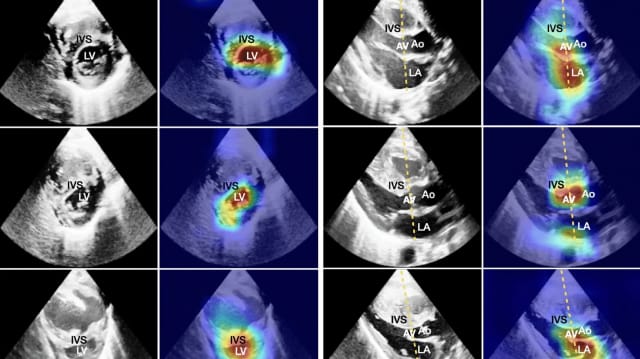

In diesen Herz-Ultraschall-Bilder sind auffällige Stellen markiert: Die oberen Bilder zeigen an, dass keine pulomonale Hypertonie vorliegt, in der mittleren Reihe ist eine milde Form vorhanden, und in der unteren Reihe handelt es sich um eine schwere Erkrankung. So können sich Ärztinnen und Ärzte genau anschauen, welche Stellen oder Eigenschaften des Herzens und seiner Gefässe dem Computer-Modell auffällig erschienen. | International Journal of Computer Vision

Auffälliges markiert

Ihr Modell markiert deshalb in den Ultraschallbildern diejenigen Bereiche, aufgrund derer es seine Einteilung getroffen hat.

Ärztinnen und Ärzte können sich also genau anschauen, welche Stellen oder Eigenschaften des Herzens und seiner Gefässe dem Modell auffällig erschienen.